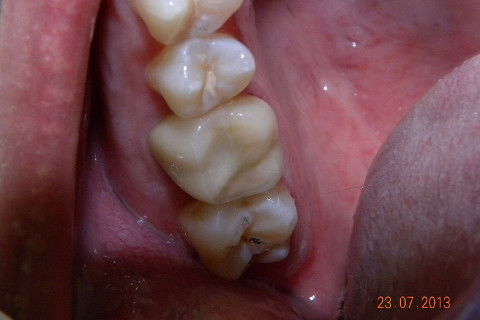

2ª CONSULTA: Coroa pronta e-max

2ª CONSULTA: Coroa e-max instalada

Caso de fratura de um trabalho protético preexistente, não sei qual e nem o paciente soube informar. Na minha opinião caso indicado para pinos metalicos rosqueáveis, muitos colegas condenam e indicam para esse caso pino metálico fundido. Creio que o fato de você fazer o preenchimento do núcleo com resina e depois cimentar com um cimento resinoso onde vai haver adesão química nas duas partes, formando um corpo único entre núcleo e coroa, ofereça uma resistência muito maior do que uma linha de cimentação onde a retenção é apenas mecânica. Continuando... 1ª CONSULTA: Pinos metálicos rosqueáveis, preenchimnto em resina, coroa provisória e moldagem com sil de adição (para qe possamos vazar o troquel e no mesmo molde o modelo para aplicação da cerâmica. 2ª CONSULTA: restauração de uma cárie no dente 17 (eu sei que era para ter feito na 1ª consulta por conta do ponto de contato, mas não deu tempo) e cimentação com cimento resinoso da 3M e caso encerrado. A radiografia não é desse caso, mas de uma caso igualzinho, a única diferença foi que envolveu cirurgia periodontal, veja como há a formação de um corpo único entre, núcleo e coroa. Um abraço. Jadson.